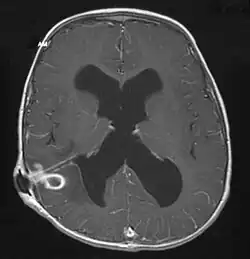

Die häufigste Komplikation ist die Raumforderung mit Erhöhung des Hirndrucks. Hierbei können erneut neurochirurgische Interventionen erforderlich werden, insbesondere eine Liquordrainage oder in Einzelfällen eine Kraniektomie.

Zunächst ist eine bildgebende Untersuchung erforderlich, die zumeist mittels kontrastmittelgestützter Computertomographie oder Magnetresonanztomographie erfolgt. Hier sind in den meisten Fällen der entzündliche Herd, das umgebende Ödem sowie eine Anreicherung des Kontrastmittels zu erkennen.